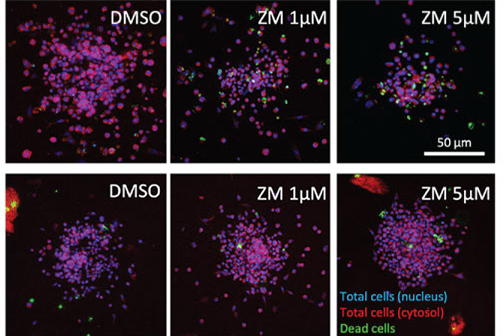

Study Reports Blocking Key Enzyme Boosts Anti-Cancer T-Cell Responses and Resistance to Immunosuppression

A study led by LSU Health New Orleans cancer researchers describes a novel therapeutic strategy to overcome tumor-induced immunosuppression. For the first time, the research team identified a critical immunosuppressive pathway and a promising approach to intervene, protecting the ability of T-cells to attack cancer cells. Results are published in Frontiers in Immunology. More